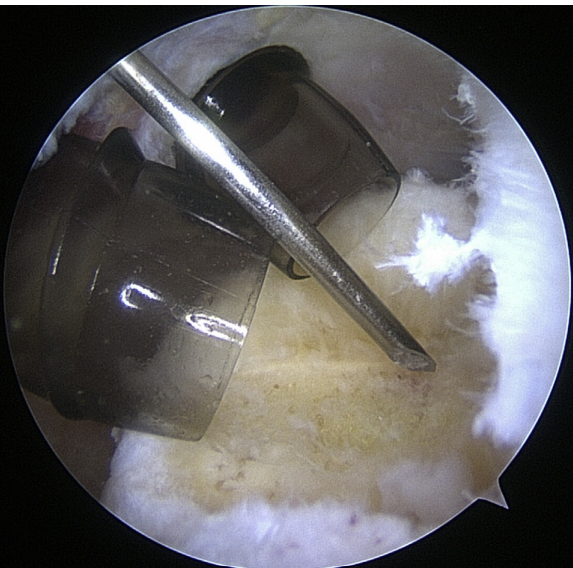

Instrumentation

When it comes to shoulder arthroscopy, the most common arthroscope utilized is the 4.0 mm 30 scope. A 30-magnification scope is sufficient for most situations. An arthroscopic-assisted coracoclavicular reconstruction, subscapularis repairs, Remplissage procedures, glenohumeral ligament lesions, and humeral avulsion can all benefit from the use of a 4.0-mm 70 arthroscope, which should always be on hand. There should be a large selection of cannulas accessible, and they will differ according on the operation being carried out.25

As the principal penetrating instruments, 5.5-mm blunt-tipped cannulas are often used for portal insertion. Blunt tips are preferred to reduce the likelihood of iatrogenic harm, especially to articular cartilage. Because they are easily passable by the majority of arthroscopy passing devices, 8.25-mm cannulas are often employed for “instrumentation” portals. In addition, cannulas of 6.5 mm or less are commonly used in suture management. Cannulas that are threaded or have locking mechanisms are preferable since they are less likely to come free from the joint. In most cases, one of two methods can be employed: gravity or a pump system. Sufficient management of pressures, usually approximately 60 mm Hg, is necessary to avoid significant soft-tissue edema, which can complicate the use of cannulas and instruments.25

Standard Portal Placement

A traditional posterior portal would be placed at the “soft spot” of the infraspinatus’s raphe. The standard placement is 2 centimeters inferior and 2 centimeters medial to the posterolateral border of the acromion, however this can change according to the patient’s size. It is possible to make a portal incision after inserting an 18-gauge spinal needle into this region to roughly follow the correct course. The posterior capsule is shattered by inserting a blunt trocar into the joint and directing it toward the coracoid.6

Preliminary surgical planning will establish the exact location of the anterior portal. Arthroscopy techniques for rotator cuff or biceps tenodesis usually include positioning the anterior portal centrally in the rotator interval, near the subscapularis tendon. It is common practice to use two anterior portals while performing arthroscopy on labral disease. The anteroinferior portal, which is often the working portal, is typically located around the subscapularis tendon. An extra portal called the anterosuperior portal may be used for suture inspection or shuttletling without damaging the supraspinatus tendon. Its location is directly above the biceps tendon or just slightly ahead of it. A common technique for creating these portals is the “outside-in” approach, which involves inserting a spinal needle under direct arthroscopy view to determine the correct portal location.6

Setup

The coracoid, acromioclavicular joint, clavicle, and acromion are all marked on the skin. If subacromial work is going to be performed, the subacromial bursa may be infiltrated with up to 30 cm3 of a mixture of 0.25% bupivacaine and epinephrine. A standard posterior portal is the typical site of access to the subacromial area and glenohumeral joint. The typical placement of this opening is 2 centimeters medial and 2 centimeters distal to the posterolateral border of the acromion. Palpating the soft tissues of the posterior glenohumeral joint is a common way to confirm the proper position. An anterior portal develops after the joint has been inserted. Figure 4 shows that the surgeon has the option of employing a spinal needle to perform it from the outside in or an inside out approach, depending on his or her choice. The anterosuperior portal is located just off the outside edge of the acromion. You may find the anteroinferior portal directly on the side of the coracoid. One centimeter below the anteroinferior portal is the 5 o’clock portal, which is defined as passing through the subscapularis tendon. Scientists say this entry point is the most common and least invasive as it mimics neurovascular systems. Any anterior portal may be used to conduct basic shoulder arthroscopy. Figure 5 shows the setup of both anterior portals for biceps tenodesis, subscapularis repairs, and labral repairs. For posterior labral repairs, spinal needle localization allows for the creation of an auxiliary posterolateral portal situated immediately distal to the posterolateral limit of the acromion. Anterior positioning of the Wilmington portal, one centimeter laterally to the posterolateral margin of the acromion, is recommended for superior labral repairs. The posterolateral and Wilmington portals are types of trans-rotator cuff tendon access points. Cannulas with the smallest diameters necessary should be used.25

The subacromial region may be accessed via the posterior portal if needed after any intra-articular procedures are finished. Spinal needle localization allows for the creation of a lateral portal, typically 2 cm laterally to the acromion’s lateral border and aligned with the clavicle’s posterior border (Figure 6). For any subacromial surgery, pre-positioned anterior portals may be used (Figure 7). An extra Neviaser portal may be made underneath the spinal needle localization, precisely below the acromioclavicular joint, if that becomes essential. This may be useful for a variety of suture procedures, including those involving the superior labrum, the rotator cuff, and the decompression of the suprascapular nerve (Figure 8).25